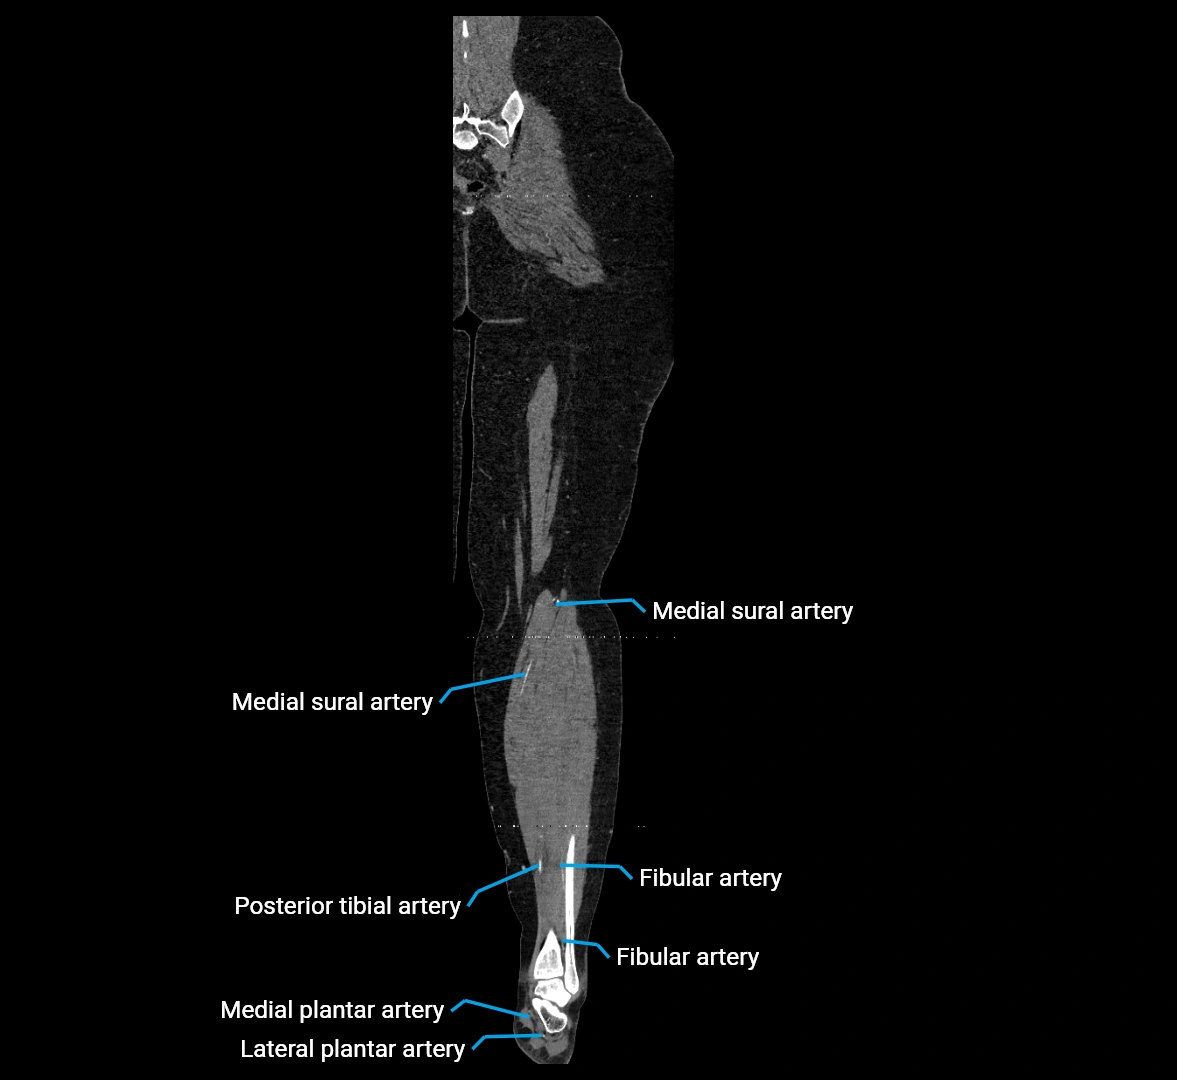

CT images

image

Contrast-enhanced CT (CTA):

• Gold standard for abdominal aortic imaging

• Provides excellent detail of lumen, wall, aneurysm, thrombus, and branch vessels

• Multiplanar and 3D reconstructions help in aneurysm measurement, stent graft planning, and dissection evaluation